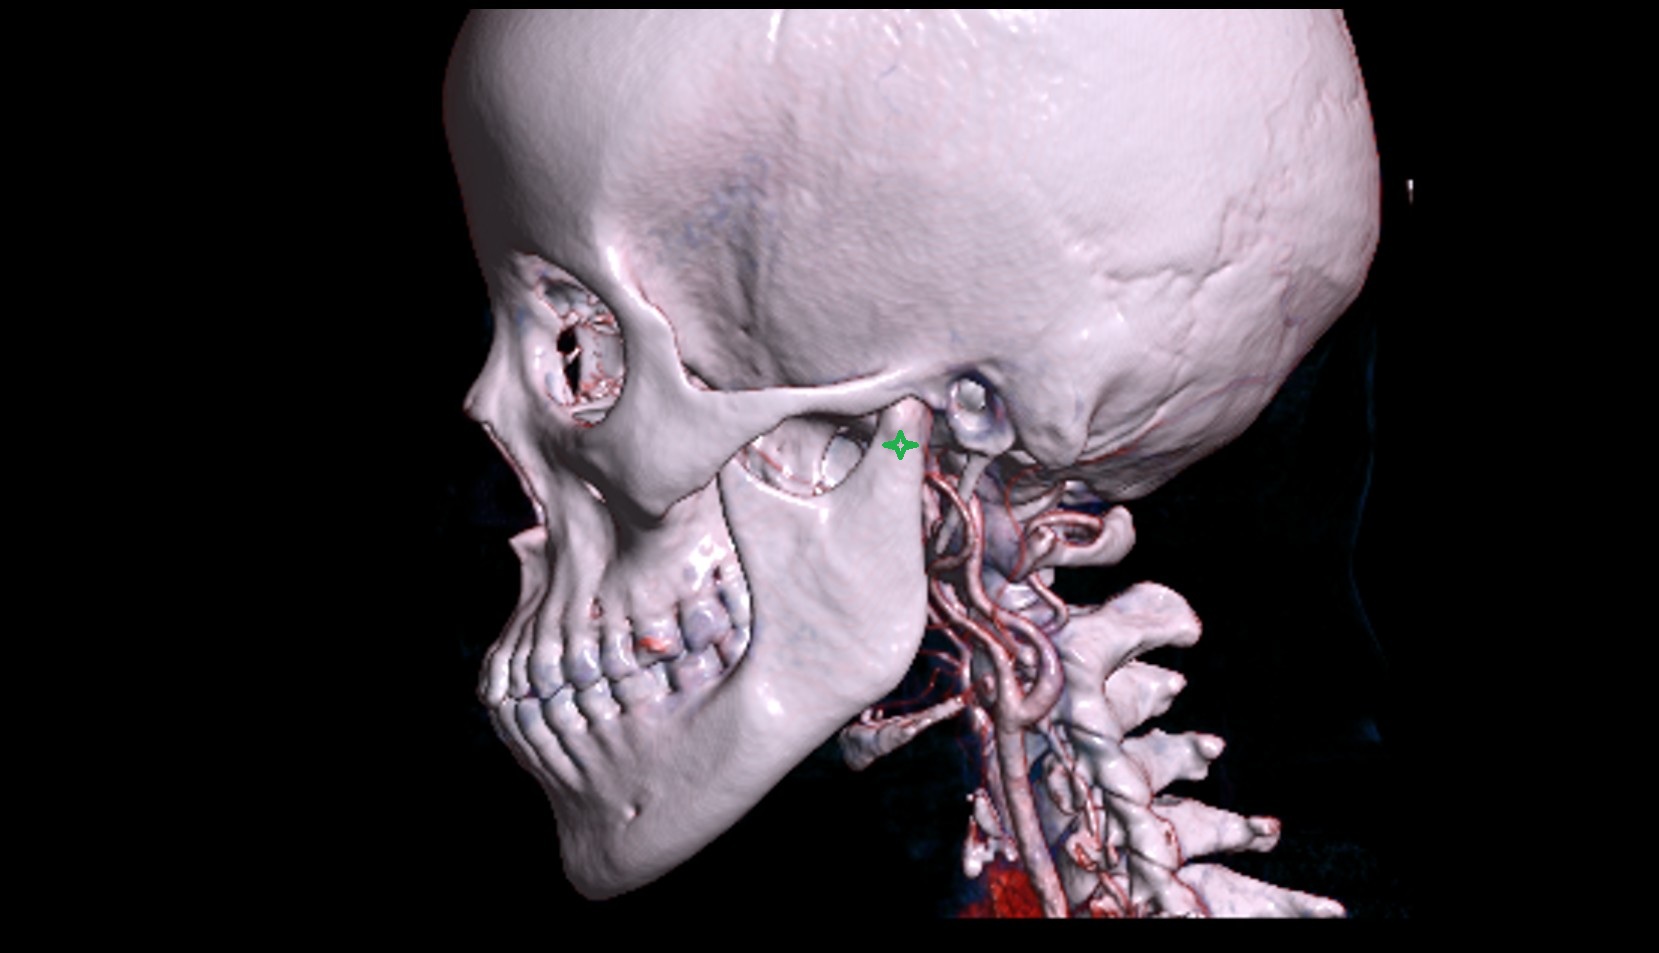

- Temporomandibular joint

- Mandibular condyle

- Mandibular fossa

- Mastoid process

- Squamous part of temporal bone

- Zygomatic process of temporal bone

- Zygomatic arch